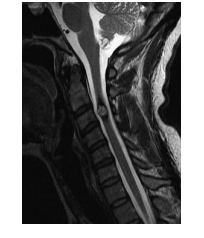

A 15-year-old boy presents with neck pain and bilateral upper limb weakness. MRI is shown below.Which one of the following is most likely?

e. Type III juvenile (extradural-intradural) AVM

Juvenile spinal AVMs are extremely rare lesions.

These lesions are again true AVMs, with an intramedullary niduswhichmay occupy the entire spinal canal at the involved level. Cord tissue is present within the AVM interspaces. Extramedullary and even extraspinal extension of the lesion is possible.

Juvenile AVMs are large and complex lesions, with

multiple arterial feeding vessels often arising from

different cord levels. Hemodynamically, this lesion

manifests both high flow and high pressure, often

yielding an auscultatable spinal bruit over involved

levels. They occur most commonly in adolescents

and young adults. Presentation and treatment are

similar to Type II AVMs; however, prognosis for

these lesions, considering their size and vascular

complexity,is understandably very poor.MRimaging typically demonstrates prominent flow voids

suggestive of underlying vascular malformation.

Edema or gliosis can also be seen on MR imaging